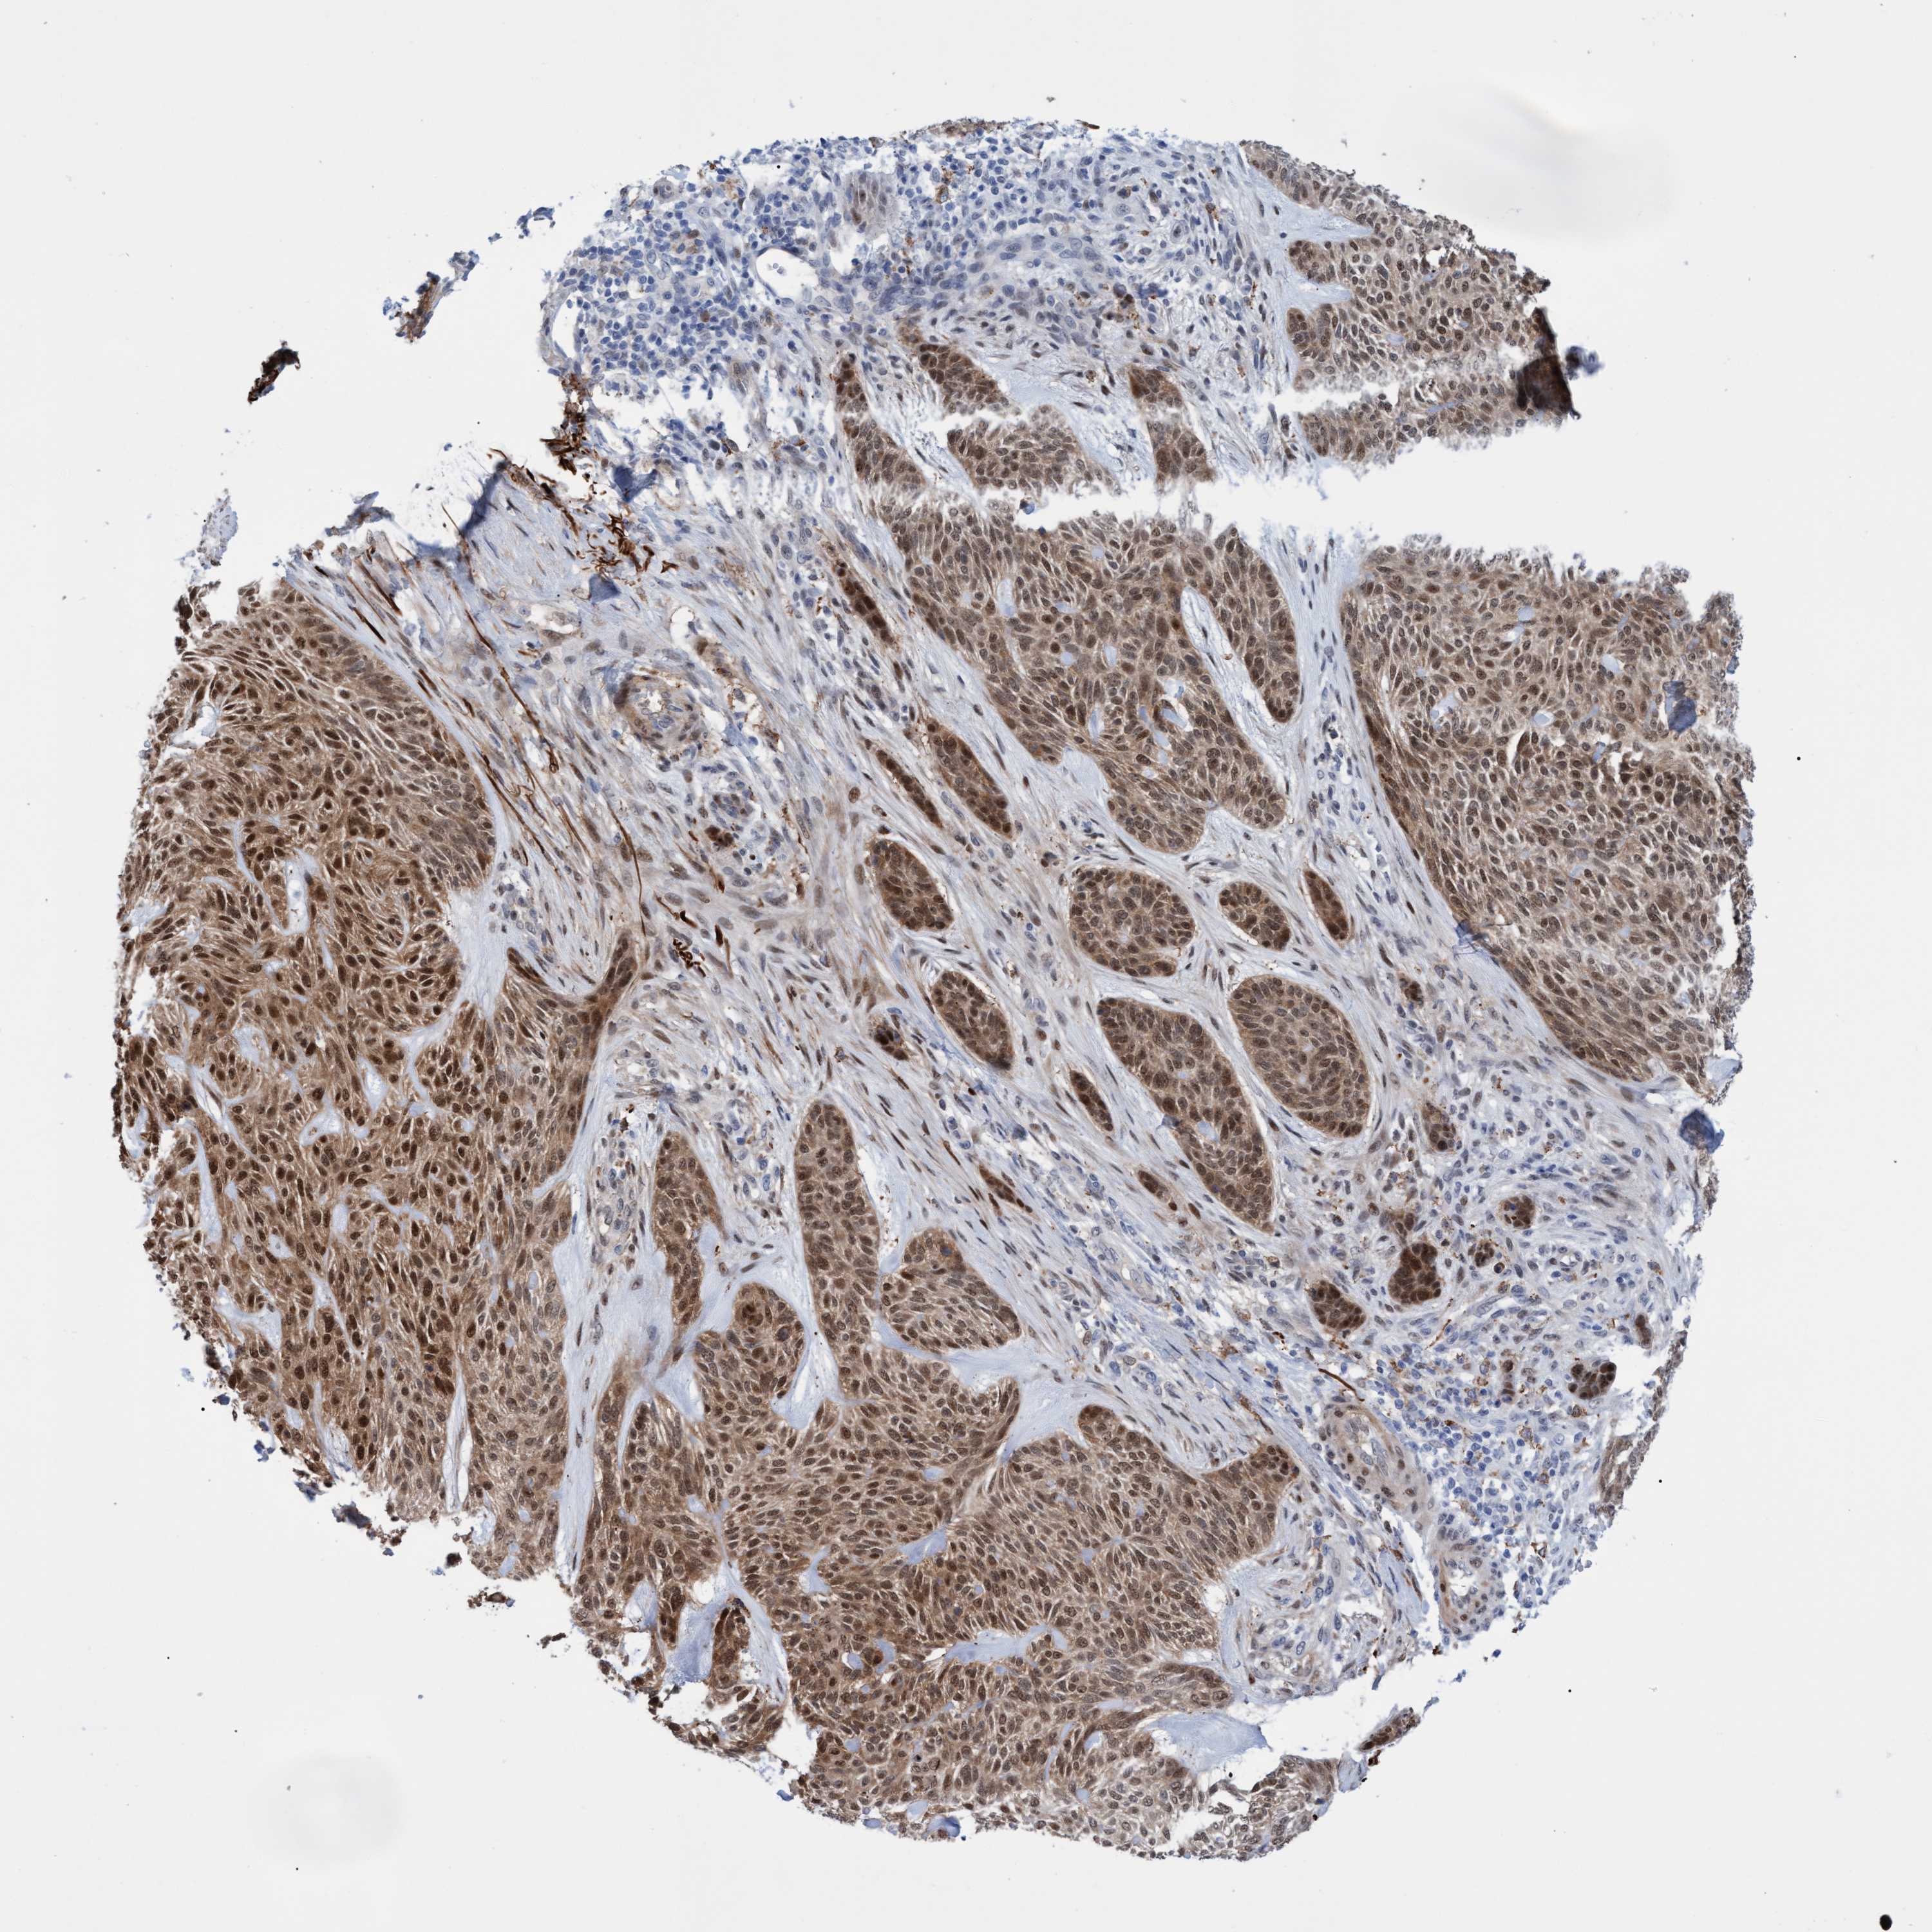

SKIN CANCER - Protein expressioni

A mouse-over function shows sample information and annotation data. Click on an image to view it in a full screen mode. Samples can be filtered based on level of antibody staining by selecting one or several of the following categories: high, medium, low and not detected. The assay and annotation is described here.

Antibody staining in the annotated cell types in the current human tissue is reported as not detected, low, medium, or high, based on conventional immunohistochemistry profiling in selected tissues. This score is based on the combination of the staining intensity and fraction of stained cells.

Each image is clickable and will lead to virtual microscopy that enables deeper exploration of all samples and also displays staining intensity scores, fraction scores and subcellular localization as well as patient and tissue information for each sample.

Antibody HPA023139

Basal cell carcinoma

Squamous cell carcinoma, NOS

Squamous cell carcinoma, metastatic, NOS